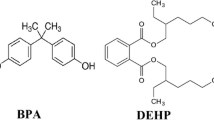

Mycotoxins are secondary fungal metabolites which pose a significant threat for global food and feed security due to their adverse effects on human and animal health (Viegas et al. 2019), high chemical stability and ubiquitous presence (Zhou et al. 2017). Simultaneous exposure to several mycotoxins produced by the same or different fungal species exacerbates the risk of food and feed toxicity (Knutsen et al. 2017; Payros et al. 2016). According to research, plant materials are often contaminated with both DON and ZEN, and the health risks associated with simultaneous exposure to both mycotoxins constitute an interesting topic of study (Medina et al. 2017; Zachariasova et al. 2014).

Present in plant material, DON and ZEN belong to a large group of structurally related sesquiterpenoids which are produced by various fungal species, including Fusarium, Myrothecium, Cephalosporium, Verticimonosporium and Stachybotrys (Zhou et al. 2017). To date, the following mechanisms of toxicity of this mycotoxins have been identified in cells or proteins: (i) DON binds to the 60S ribosome subunit at the molecular level and induces ribotoxic stress which activates protein kinase and, consequently, inhibits protein synthesis, provokes endoplasmic reticulum stress (You et al. 2021), cell signalling, cell differentiation, cell proliferation and cell death (Gajęcka et al. 2021; Pavros et al. 2016); (ii) ZEN exerts toxic effects by binding to and activating both ERs, disrupting the cell cycle and inducing DNA fragmentation, which leads to the production of micronuclei and chromosomal aberrations (Gajęcka et al. 2020; Knutsen et al. 2017; Payros et al. 2016; Shanle and Xu 2010).

The physiological functions of endogenous and exogenous oestrogens are modulated mainly by two subtypes of ERs: ERα and Erβ (Paterni et al. 2014). These receptors are present in the cell nucleus where they regulate the transcription of target genes by binding to DNA regulatory sequences. Both subtypes of ERs are expressed in numerous cells and tissues where they regulate specific processes (Gruber-Dorninger et al. 2023; Knutsen et al. 2017). ERα is found in various tissues of the reproductive system, bones, adipose tissues and liver where it controls lipid deposition (Chen and Madak-Erdogan 2018; Yasrebi et al. 2017). ERβ occurs mainly in the prostate epithelium, urinary bladder, ovarian granulosa cells, colon, adipose tissue, immune system and liver, and it is responsible for regulating glucose and lipid metabolism (Chen and Madak-Erdogan 2018; Paterni et al. 2014).